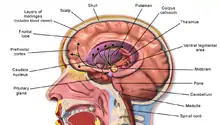

Alcohol-related brain damage[1] alters both the structure and function of the brain as a result of the direct neurotoxic effects of alcohol intoxication or acute alcohol withdrawal. Increased alcohol intake is associated with damage to brain regions including the frontal lobe,[2] limbic system, and cerebellum,[3] with widespread cerebral atrophy, or brain shrinkage caused by neuron degeneration. This damage can be seen on neuroimaging scans.[4]

Frontal lobe damage becomes the most prominent as alcoholics age and can lead to impaired neuropsychological performance in areas such as problem solving, good judgment, and goal-directed behaviors.[2] Impaired emotional processing results from damage to the limbic system. This may lead to troubles recognizing emotional facial expressions and "interpreting nonverbal emotional cues".[2]

Adolescents are much more vulnerable to alcohol-related brain damage in the form of persistent changes in neuroimmune signalling from binge drinking.[8] The endocrine system includes the hypothalamic–pituitary–adrenal axis, the hypothalamic–pituitary–gonadal axis, the hypothalamic–pituitary–thyroid axis, the hypothalamic–pituitary–growth hormone/insulin-like growth factor-1 axis, and the hypothalamic–posterior pituitary axis, as well as other sources of hormones, such as the endocrine pancreas and endocrine adipose tissue. Alcohol abuse disrupts all of these systems and causes hormonal disturbances that may result in various disorders, such as stress intolerance, reproductive dysfunction, thyroid problems, immune abnormalities, and psychological and behavioral disorders.[9]

The cerebral atrophy that alcoholics often present with is due to alcohol induced neurotoxicity.[6][10] Evidence of neurodegeneration can be supported by an increased microglia density and expression of proinflammatory cytokines in the brain. Animal studies find that heavy and regular binge drinking causes neurodegeneration in corticolimbic brain regions areas which are involved in learning and spatial memory. The corticolimbic brain regions affected include the olfactory bulb, piriform cortex, perirhinal cortex, entorhinal cortex, and the hippocampal dentate gyrus. It was found that a heavy two-day drinking binge caused extensive neurodegeneration in the entorhinal cortex with resultant learning deficits in rats.[5]

Higher order functioning of the cerebral cortex is organized by the cerebellum. In those with cerebral atrophy, Purkinje cells, or the cerebellar output neurons, in the vermis are reduced in number by 43%.[7] This large reduction in Purkinje cells causes a decrease in high order cerebral cortex organization. The cerebellum is also responsible for refining crude motor output from the primary motor cortex. When this refinement is missing, symptoms such as unsteadiness and ataxia[7] will present. A potential cause of chronic alcoholic cerebellar dysfunction is an alteration of GABA-A receptor. This dysfunction causes an increase in the neurotransmitter GABA in cerebellar Purkinje cells, granule cells, and interneurons leading to a disruption in normal cell signaling.[7]

In Korsakoff patients, MRI shows atrophy of the thalamus and mamillary bodies. PET showed decreased metabolism, and therefore decreased activity in the thalamus and other diencephalon structures.[13] Uncomplicated alcoholics, those with chronic Wernicke's encephalopathy (WE), and Korsakoff psychosis showed significant neuronal loss in the frontal cortex, white matter, hippocampus, and basal forebrain.[13] Uncomplicated alcoholics were seen to have a shrinkage in raphe neurons, the mamillary bodies, and the thalamus.[13]